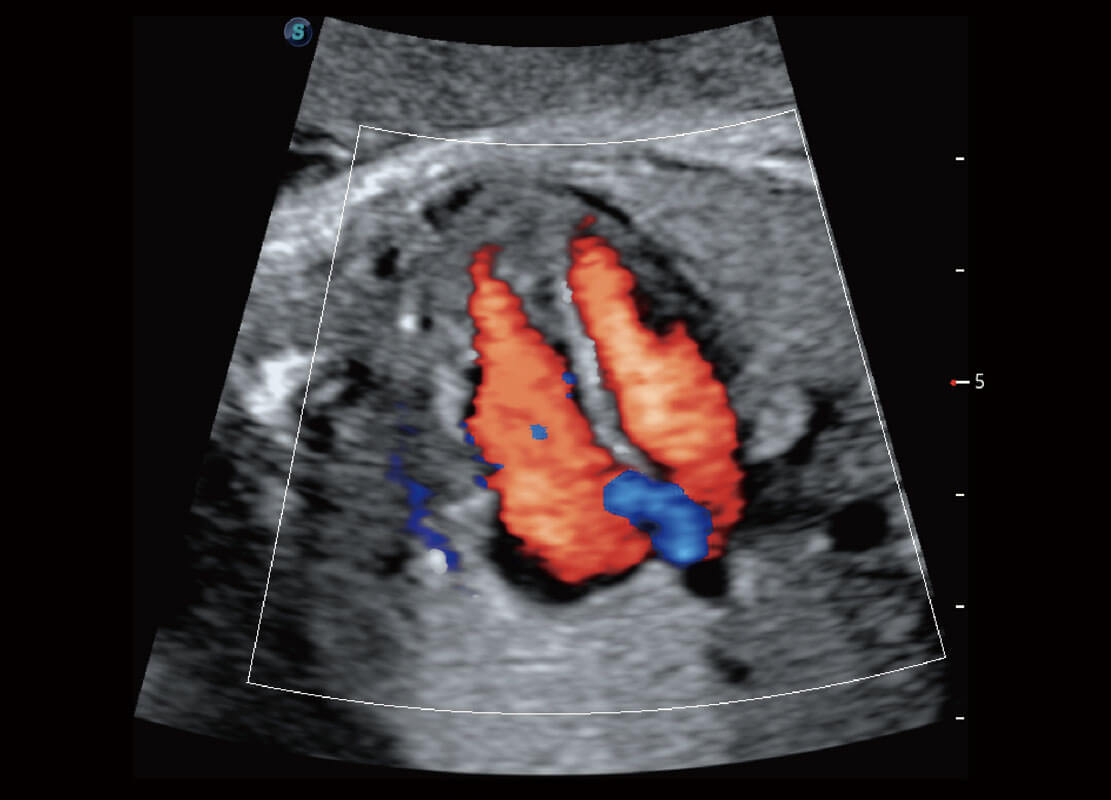

P60在胎儿早孕期超声筛查中为您带来优异的图像质量。

早孕-胎心